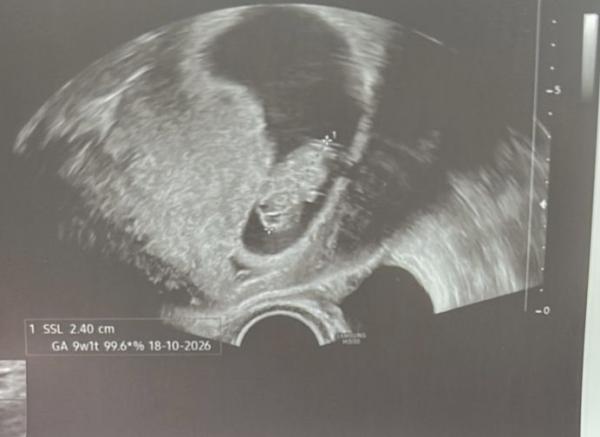

Hallo zusammen 🙋🏼‍♀️ bin zwar erst in der 10. SSW, aber kennt sich jemand aus mit der Ramzi und nub Methode aus ? Erkennt ihr was auf den US-Bilder ? Liebe Grüße  Anja